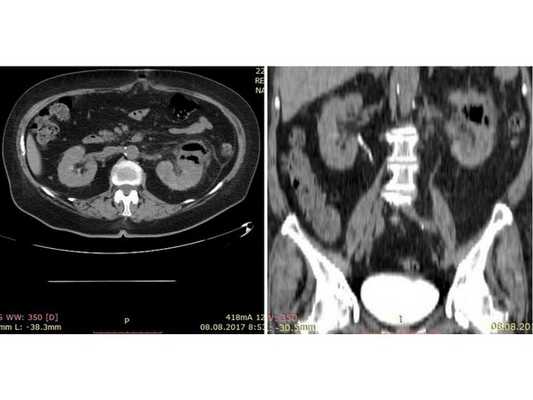

Результат мультиспиральной КТ: видны изменения левой почки, характерные для эмфизематозного пиелонефрита, функция левой почки отсутствует

(Слева) КТ без контрастирования, аксиальная проекция: большое скопление газа В в правой почке. Этот признак характерен для эмфизематозного пиелонефрита. Скопления жидкости нет. КТ-метод выбора для постановки диагноза и оценки распространения газа.

(Справа) УЗИ правой почки в сагиттальной плоскости: у этого же пациента визуализируются эхо-сигналы в паренхиме почки, ассоциированные с «грубой акустической тенью».